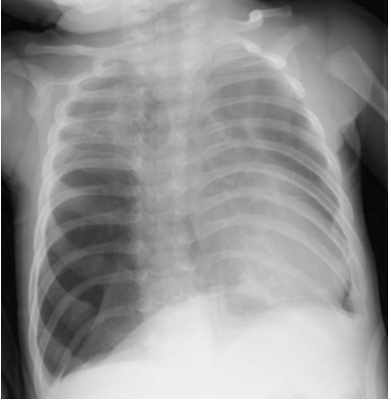

So he arrived at his local hospital where they noticed he was breathing pretty fast, although his saturations were surprisingly normal. They started a bit of oxygen hoping it would help the work of breathing they were seeing. And they did a chest X-ray.

Now, here’s the X-ray the kid initially had…..

I don’t know, there’s just something about it that makes me think it’s not normal …

What do you think? Where is the pathology? Right or left?

So now the patient has their diagnosis and it’s congenital lobar emphysema. You can really see on the CT how that right middle lobe is pretty much everywhere and probably not superb at doing the job of normal lung. The kid is getting by on not much left lung and not much of the other bits of the right lung.